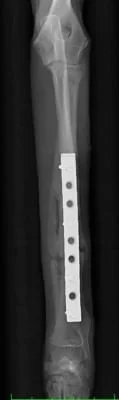

術後8週間で骨癒合の最終チェックを行いました。

その後、紹介いただいた先生もとで去勢手術と同時にネジの間引きを実施しています。

内固定の全抜去を実施する場合、少なくとも術後2週間くらいは外固定の再設置と安静が必要となります。

螺子(ネジ)の間引きだけなら術後の安静も外固定も必要ありません。

右前肢

*写真なので写りこみをカットしています。

橈骨・尺骨ともに癒合してますし、

橈骨の髄腔もきちんと確認できます。

極端な骨硬化像も認めないので経過観察終了としました。